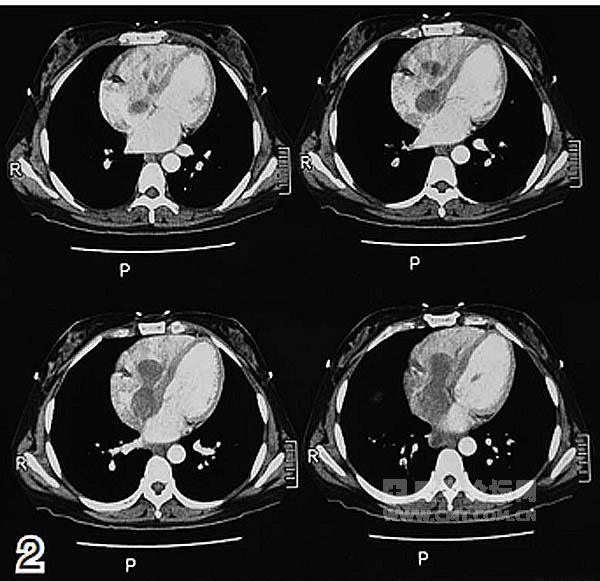

辅助检查:CT示腹盆腔巨大肿块;右侧髂静脉、下腔静脉、右心房及右心室瘤栓形成;右肾、双侧输尿管、膀胱、血管及消化道均受压推移。实验室检查示癌抗原125(CA125)为44.2 IU/ml,神经元特异性烯醇化酶(NSE)为17.0 ng/ml,雌二醇为1486 pmol/L。

放射科:该患者的CT及磁共振成像(MRI)检查显示,腹盆腔内有巨大不规则软组织密度影,边界不清,病灶推压临近肠管、胰腺、右肾及膀胱,右侧髂静脉、下腔静脉、右心房及右心室内可见充盈缺损影,考虑子宫平滑肌瘤病累及下腔静脉及右心房(图1~2)。